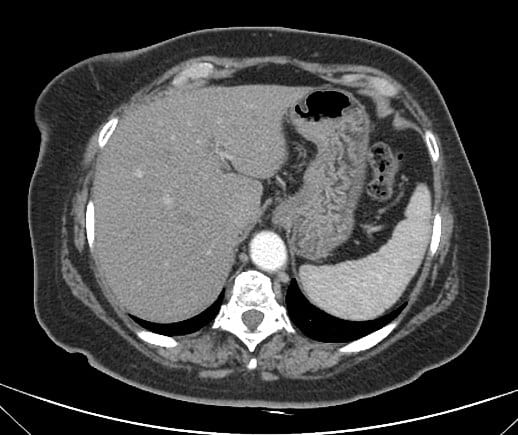

Túi thừa dạ dày

» Thông tin: Nữ giới – 50 tuổi.

» Lâm sàng: Kiểm tra sức khỏe.